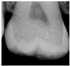

The use of near-infrared transillumination (NIRT) for early carious lesions detection has been described for more than a decade [14,17]. The enamel appears highly transparent when illuminated using NIRT and dentine appears darker than enamel because it scatters light more strongly. During the caries process, micropores are formed in the lesion due to the partial dissolution of the individual mineral crystals. These small pores behave as scattering centers, strongly scattering visible and near infrared light. Carious lesions appear dark because they scatter and absorb light more than surrounding healthy tissue [17,18,19]. Real-time images are displayed on a monitor and can be stored to allow monitoring. [20,21] The area and contrast of occlusal lesions in NIRT images can be correlated with lesion severity, and lesions that penetrate into dentine have significantly higher contrast than those in the enamel [18,22]. Several studies have shown NIRT to have higher sensitivity than BW to detect both proximal and occlusal carious lesion [23,24,25,26,27]. NIRT has also shown higher inter-examiner and intra-examiner reliability than BW [22,28,29]. The device DIAGNOcam (Kavo, Biberach, Germany) used in this study is the first marketed device that uses NIRT technology and has been tested in multiple studies [21,30,31,32].

In the present clinical study, ICDAS scores of occlusal surfaces based on clinical photographs were compared to scores based on NIRT images and digital intra-oral radiographs. The results show that more early occlusal lesions were detected using NIRT followed by clinical images, while BW scores showed mostly sound surfaces at both examinations (first and second assessments) as shown in Table 3.

A similar in vivo study [37] that compared the three methods found that most carious lesions were detected using visual examination followed by NIRT and then BWs. Our finding might be explained by the stricter criteria we used for NIRT images. We considered any visible changes in the occlusal fissure system as an early sign of demineralization based on some of our unpublished in vitro work on extracted teeth with occlusal lesions.